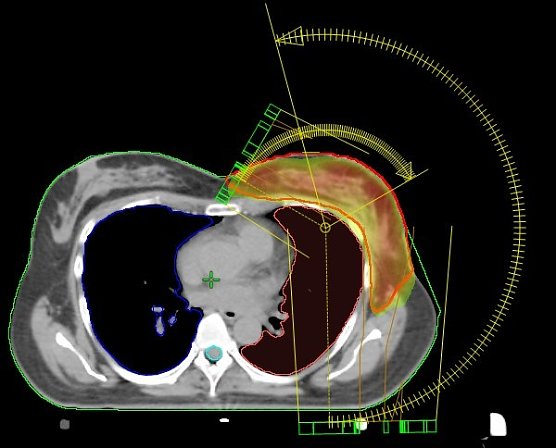

Die seit dem Jahr 2009 im Südharz Klinikum eingesetzte Bestrahlungstechnik an den Linearbeschleunigern macht es möglich, den Bereich der Bestrahlung nicht nur geradlinig, sondern auch bogenförmig maßgeschneidert zu erfassen.

Wir bestrahlen die Brust nicht standardisiert, sondern programmieren die Technik so, dass der Dosisverlauf individuell an die jeweilige Brust angepasst wird. Und das ist von Frau zu Frau immer unterschiedlich. Kollateralschäden an benachbarten Organen werden so auf ein Minimum reduziert”, berichtet der leitende Medizinphysiker Dirk Strauß.

Einzigartig in Nordhausen: VMAT-Bewegungsbestrahlungstechnik mit 2 Bögen (Nordhäuser Standardtechnik); der Hochdosisbereich erfasst ausschließlich das Zielvolumen und die umgebenden Risikoorgane werden geschont.

Was im Jahr 2009 mit den damals modernen Linearbeschleunigern in Nordhausen eingeführt wurde, das wird mit der Inbetriebnahme der neuesten Generation Ende vorigen und Anfang dieses Jahres konsequent fortgesetzt. Mit der jetzt vorhandenen Technik kann zudem die Bestrahlungszeit für die Tumor-Patienten auf rund 1,5 Minuten reduziert werden. Einmalig in der deutschen Krankenhauslandschaft, berichtet Dr. med. Wolfgang Oehler.